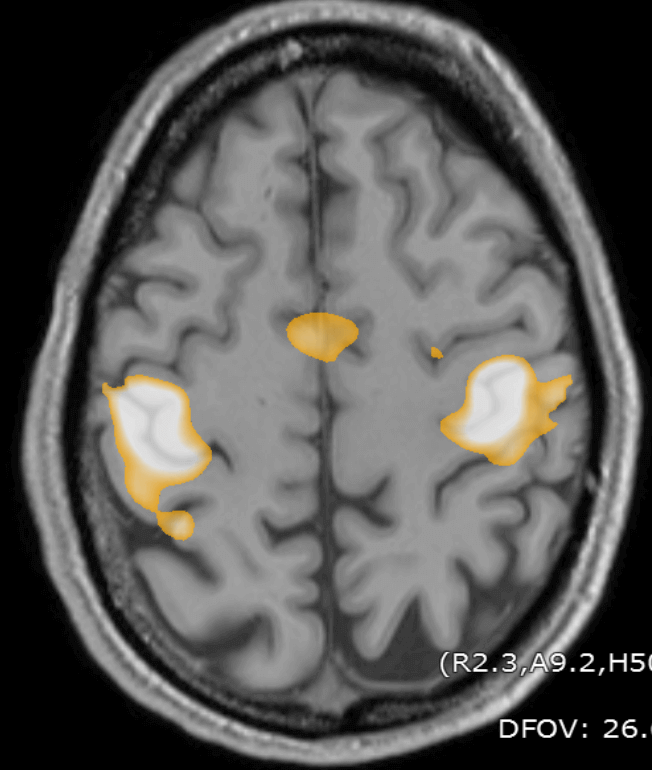

Finger movement generates a large change in BOLD signal (Blood Oxygen Level Dependent signal) in the “hand knob” on the primary motor cortex.

fMRI showing activity in the hand region of the primary motor cortex.

fMRI changes from finger movement